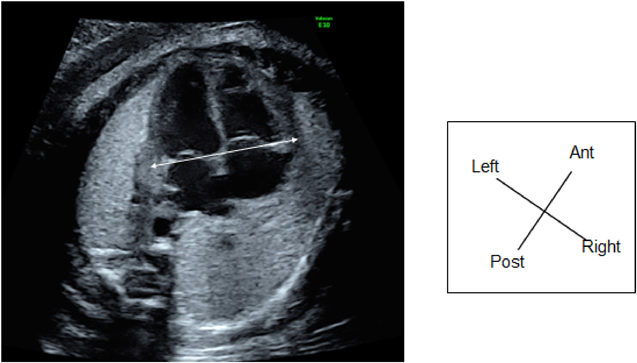

ii. Cardio-Thoracic Area Ratio

CTAR is calculated by dividing the area of the heart by the thorax area and described in percent (Fig. 6a). The heart area is measured by tracing the exterior of the pericardium, and the thorax area by tracing the exterior of the thoracic cage including the ribs and the spinal column, but not the skin or the muscles. These manual tracing is complicated and time-consuming. The so-called ellipse method (ellipse shapes approximating the areas) is often used. The normal CTAR is 20–35% (Fig. 6b). In the second or third trimester, a CTAR >35% indicates cardiac enlargement.